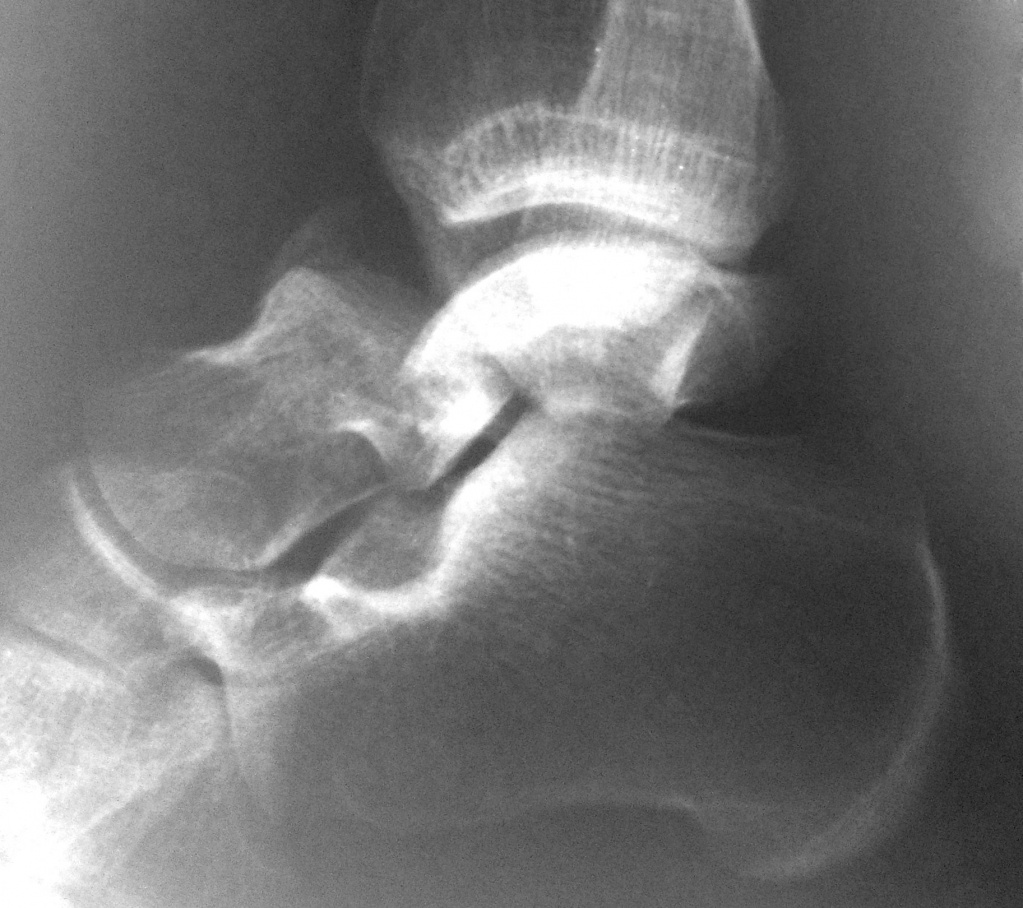

Рентгенограмма пациента с переломом таранной кости